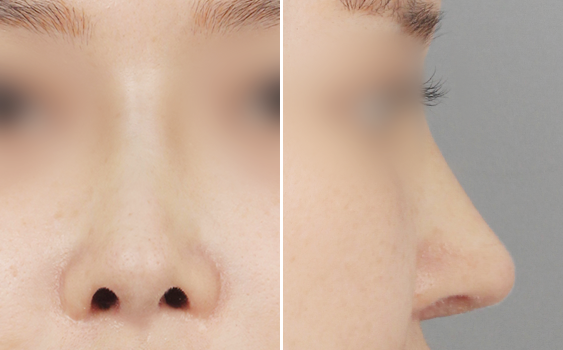

CASE01.

코 2차 수술 / 보형물 비침 및 휘어짐, 얇은 피부

수술 전

수술 후 3개월

얼굴과 밸런스를 이루는

이상적인 코라인

얼굴과 밸런스를 이루는 이상적인 코라인을 찾아서

어느 각도에서 봐도 아름다운 라인을 만들어 드립니다.